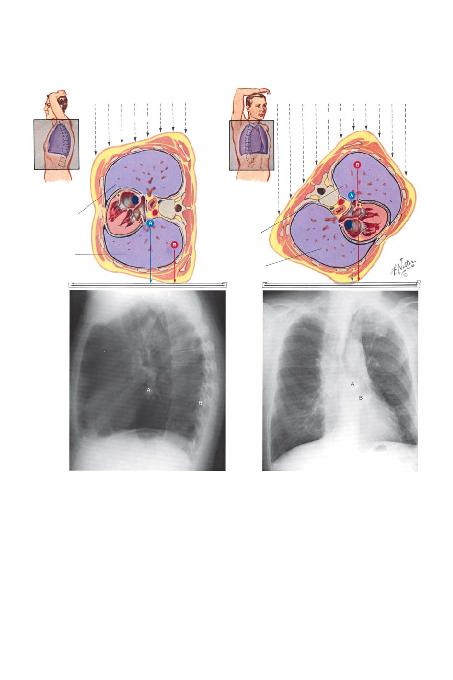

Oblik filmler yorumlan>rken kalbin önde yer

alan bir yap> oldu¤u ve dolay>s> ile sa¤ ön oblik gö-

rünümde sola ve sol ön oblik görünümde sa¤a kaya-

ca¤> ak>lda tutulmal>d>r. Arkada yer alan olan omur-

ga z>t yönde hareket eder. Akci¤er içindeki nodüller,

kalb ve omurgaya göre konumlar>ndaki de¤iflikli¤e

ba¤l> olarak önde veya arkada görülebilir. Bu du-

rum, PA filmde saptanan fakat yan filmde görülme-

yen bir nodül bulunan hastan>n incelenmesinde

özellikle yararl>d>r. Akci¤er dansitelerinin konu-

mundaki göreceli kaymalar Levha 1 ve 2'de sunul-

mufltur.

X->fl>n> demeti

Sa¤ akci¤er

Sol akci¤er

Yan Görüntü

Sa¤ Ön Oblik Görüntü